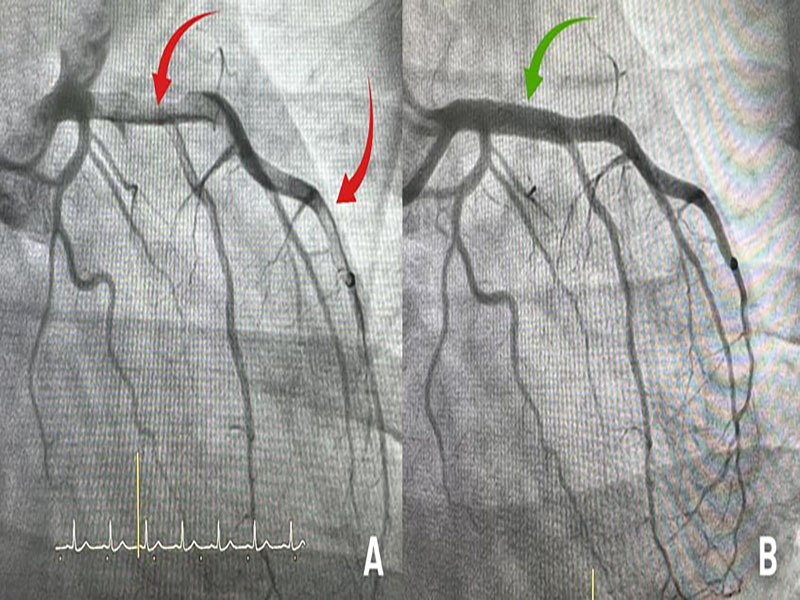

Sau vài giờ điều trị nội khoa, anh Phan giảm dần cơn đau ngực. Tuy nhiên, kết quả các cận lâm sàng liên quan (xét nghiệm men tim, đo điện tim, chụp mạch vành) xác định bệnh nhân bị nhồi máu cơ tim do động mạch liên thất trước bị huyết khối lấp tắc hoàn toàn từ lỗ xuất phát đến mỏm tim (khoảng 15 cm). Anh Phan được dùng thuốc chống đông, chuyển đến BVĐK Tâm Anh TP HCM điều trị tiếp.

Nhờ sự chuẩn bị kỹ lưỡng cùng thao tác chuẩn xác của các bác sĩ, sau 5 chu kỳ hút, hàng trăm cục huyết khối được lấy ra từ động mạch liên thất trước, mở đường cho ê kíp đặt stent kích thước 4.5×15 mm khơi thông dòng chảy. “Không chỉ ở Việt Nam mà cả trên thế giới, rất hiếm trường hợp nhiều huyết khối lấp tắc mạch vành như bệnh nhân này”, bác sĩ Minh khẳng định.